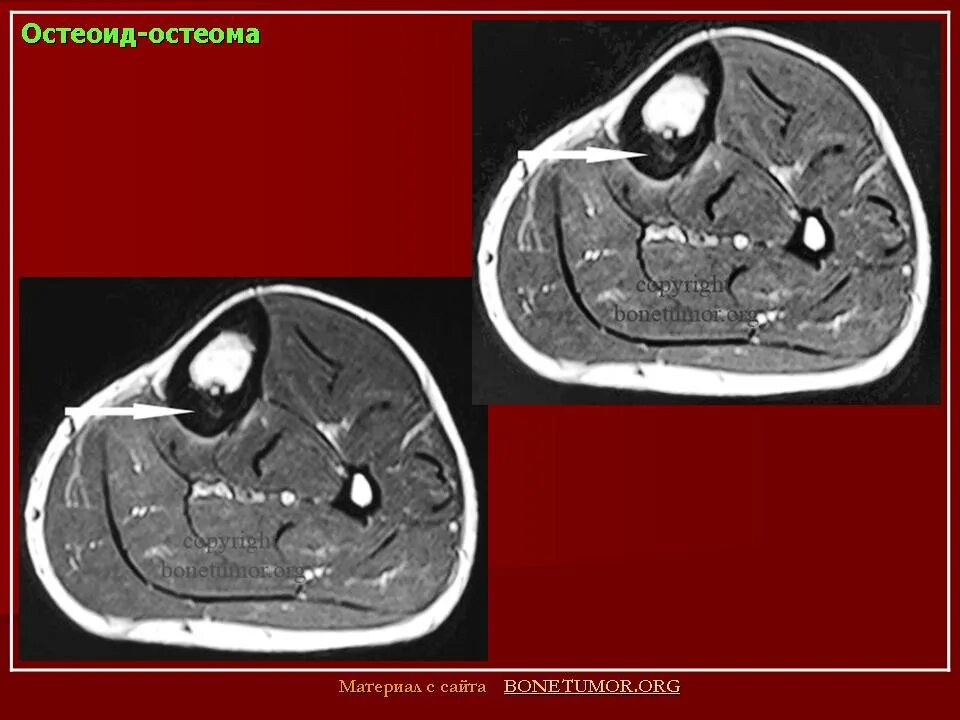

Остеома мрт